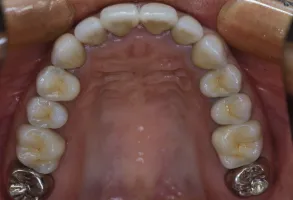

初診時

治療完了時

| 患者様のお悩み | 咀嚼障害(左下奥歯) |

| 治療法・使用素材 | 自家歯牙移植治療 |

| 患者様の年代 | 30代 |

| 治療開始年齢 | 30代 |

| 治療にかかった期間 | 6か月 |

| 性別 | 女性 |

| この治療のリスクについて | 移植歯が生着するかどうか |

| 治療にかかった費用 | 5万円 |